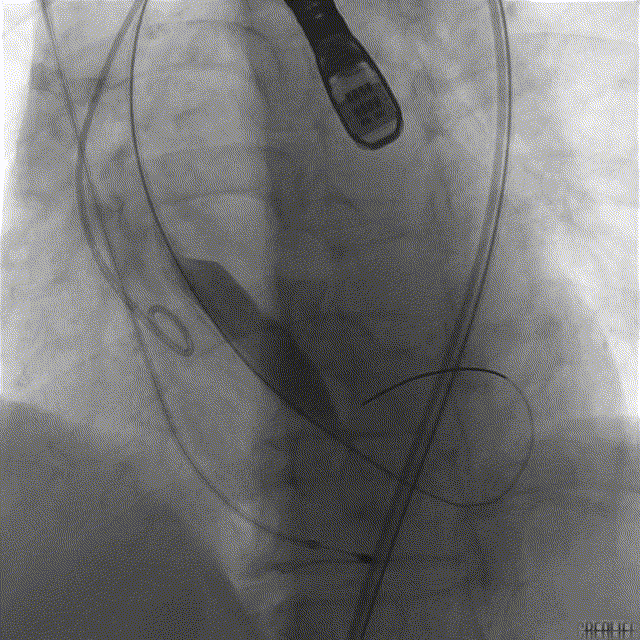

TaurusOne® 输送器顺畅过弓

造影辅助定位

精准释放

术后即时评估,患者超声下指标改善明显,无明显瓣周漏、瓣中漏;造影示瓣膜工作形态良好,无明显反流。